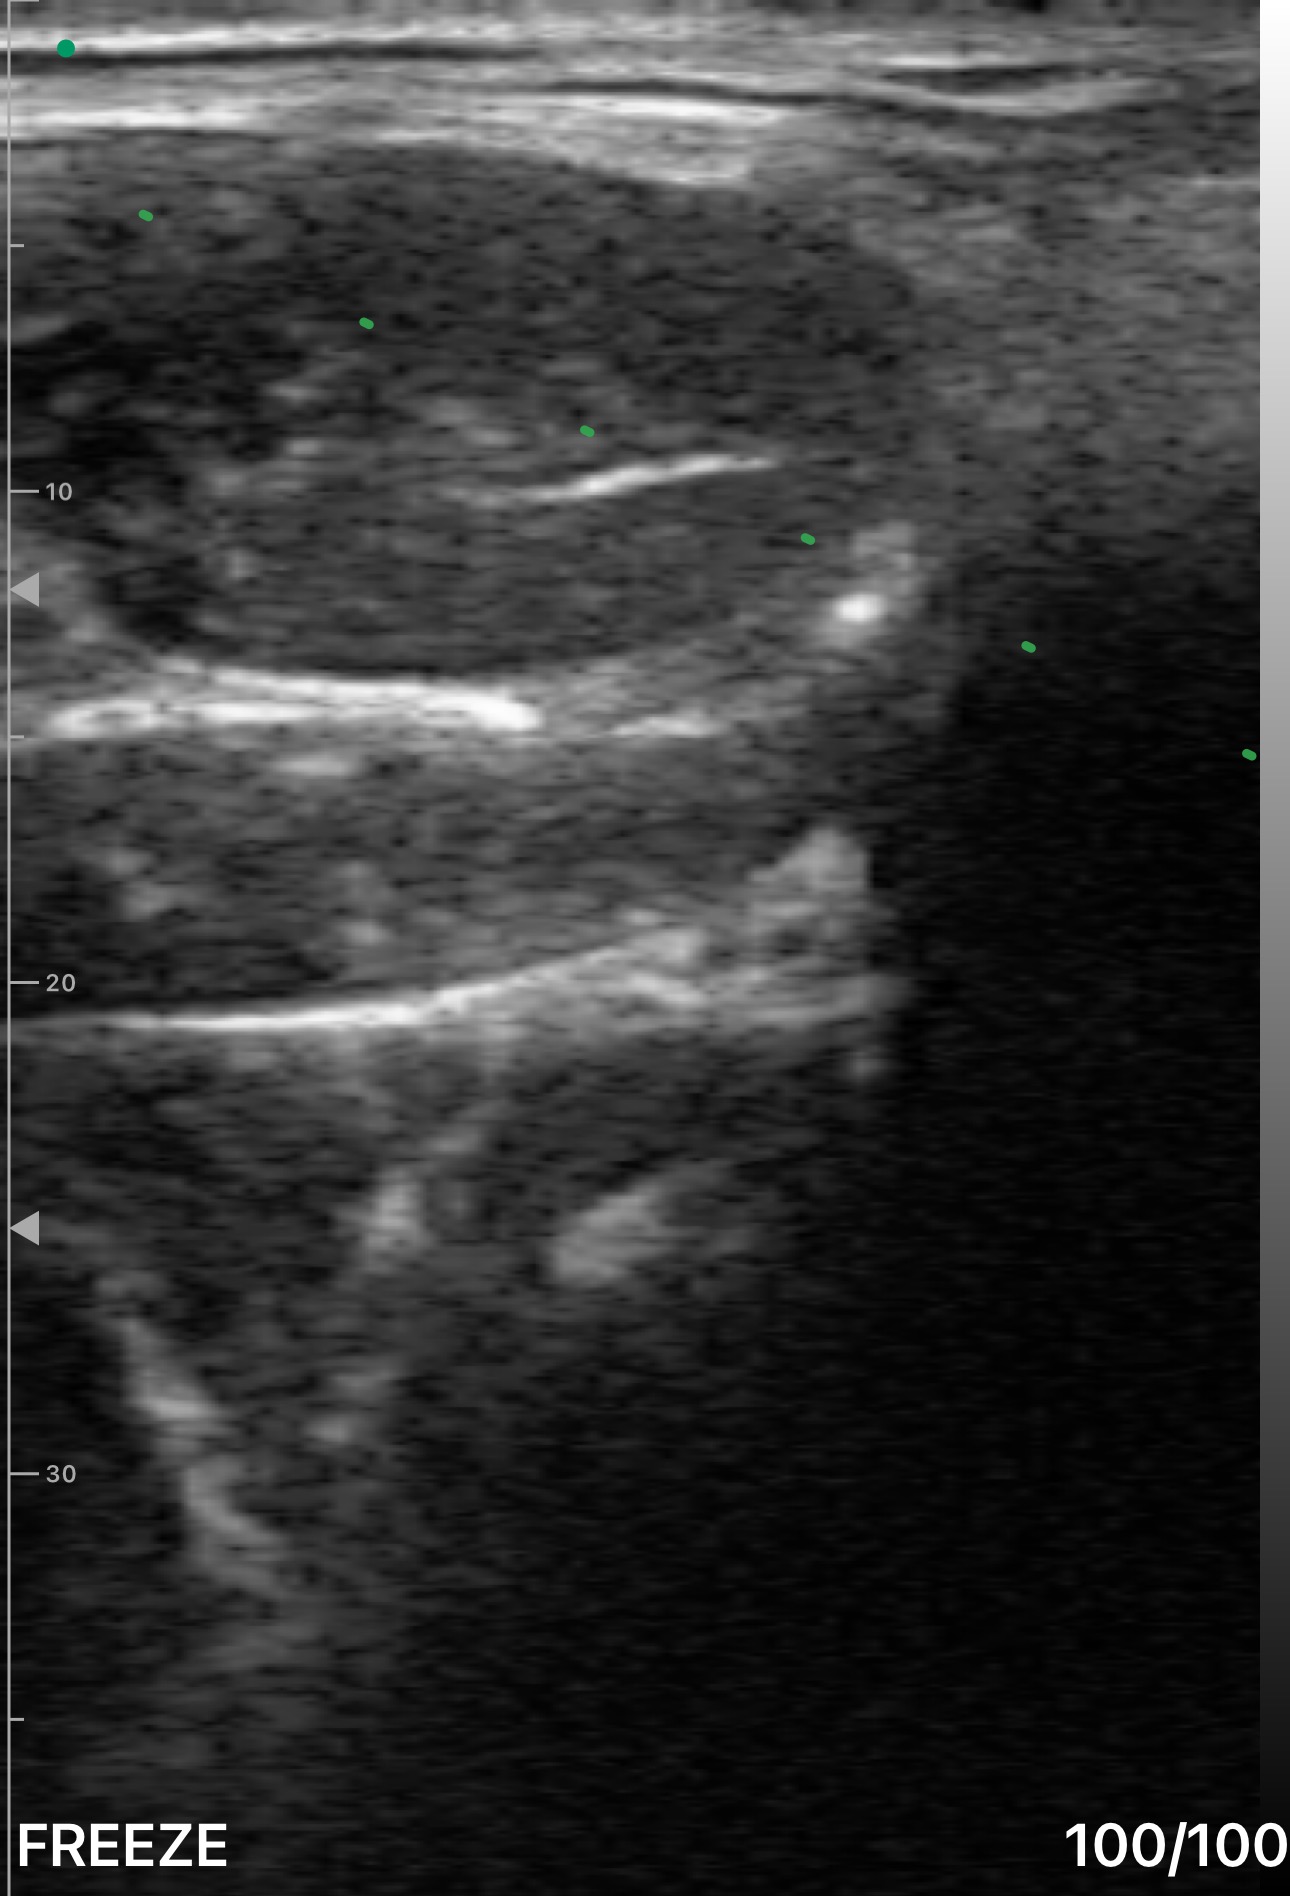

Obrazowanie ultrasonograficzne przemawia odcieniami szarości. W przeciwieństwie do fotografii, która rejestruje światło odbite od powierzchni, obraz ultrasonograficzny przedstawia fale dźwiękowe odbijające się od tkanek wewnątrz ciała. Każdy odcień opowiada historię o tym, co znajduje się pod głowicą.

Wygląd struktur w ultrasonografii zależy od ich impedancji akustycznej — czyli od tego, jaki opór stawia tkanka falom dźwiękowym. Gdy dźwięk napotyka granice między tkankami o różnej impedancji, część energii odbija się, tworząc obraz, podczas gdy reszta wędruje głębiej.

Czerń: strefa bezechowa (anechogeniczna)

Płyn wydaje się czarny, ponieważ fale dźwiękowe przechodzą przez niego z minimalnym odbiciem. Naczynia krwionośne, torbiele, zawartość pęcherza moczowego, wysięki stawowe i płyn osierdziowy — wszystkie mają ten ciemny wygląd. Gdy widzisz dobrze odgraniczony czarny obszar, Twoja pierwsza myśl powinna brzmieć: płyn.

Odcienie szarości: krajobraz tkanek miękkich

Większość tego, co będziesz badać, mieści się w spektrum szarości. Mięśnie, tkanka tłuszczowa, narządy i inne tkanki miękkie mają charakterystyczny wygląd zależny od ich wewnętrznej struktury i zawartości wody. Z praktyką nauczysz się odróżniać wątrobę od nerki, mięsień od tłuszczu i zdrową tkankę od patologii — wszystko poprzez subtelne różnice w szarości.

Jasna biel: struktury hiperechogeniczne

Struktury silnie odbijające — kość, zwapnienia, powięź i ciała obce — wyglądają na jasno białe. Powierzchnie kości są szczególnie charakterystyczne: tworzą jasną linię, za którą następuje ciemny cień, ponieważ prawie żaden dźwięk nie przenika głębiej. Ten cień akustyczny jest jednym z najbardziej rozpoznawalnych artefaktów w ultrasonografii.

Cień akustyczny

Ciemna kolumna pojawiająca się pod silnie odbijającymi strukturami, takimi jak kość czy zwapnienia. Cień powstaje, ponieważ dźwięk nie może przeniknąć przez te gęste materiały. Ten artefakt faktycznie pomaga — wyraźny, czysty cień pod powierzchnią kości potwierdza integralność warstwy korowej, podczas gdy przerwany cień może sugerować złamanie.